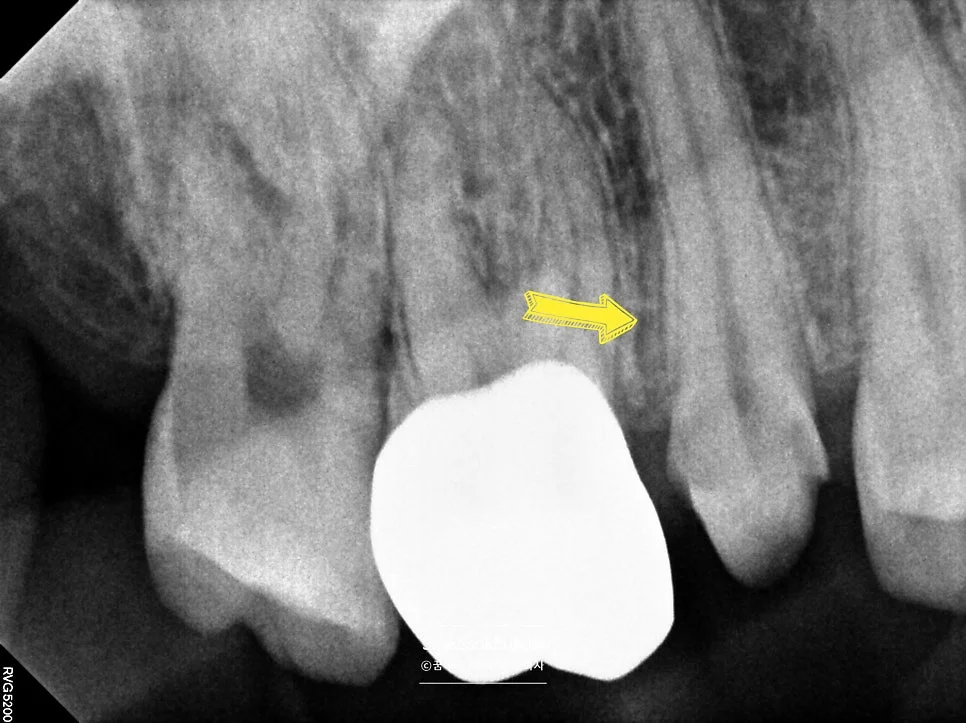

2번 치아 — 충치가 깊지만 신경치료 없이 크라운

한편 2번 치아의 충치 크기가 너무 큰데요.

당장은 찬 것에 대한 반응이 크지 않아 신경치료 없이 크라운 치료를 진행합니다. 한편, 증상이 생기면 신경치료의 가능성을 설명드리면서요ㅜ

인레이 두 개는 아무 문제 없이 접착하였는데 아까 충치가 깊었던 2번 치아가 약간 시린 증상이 있다고 합니다.

이런 경우 임시 접착을 한 후 일주일 정도 지켜보면서 증상을 확인합니다.

대략 7일 후 재내원 하셔서는 많이 시리진 않는데 불편함을 호소하시는데요.

시간이 지나며 좋아질 가능성이 있지만 혹시나 일주일, 이주일 후에도 증상이 남아 있어 그때 신경치료에 들어가느니 얼른 신경치료를 시작하여 불편함을 없애드립니다.

하루 만에 신경치료를 완료해서요!^^ — 원데이 신경치료

2nd 수면 마취 — 원데이 신경치료

신경관이 1개고 신경관이 아주 건강한 쉬운 신경치료인데요^^

뿌리 끝까지 잘 채워주면 신경치료는 완료됩니다^^